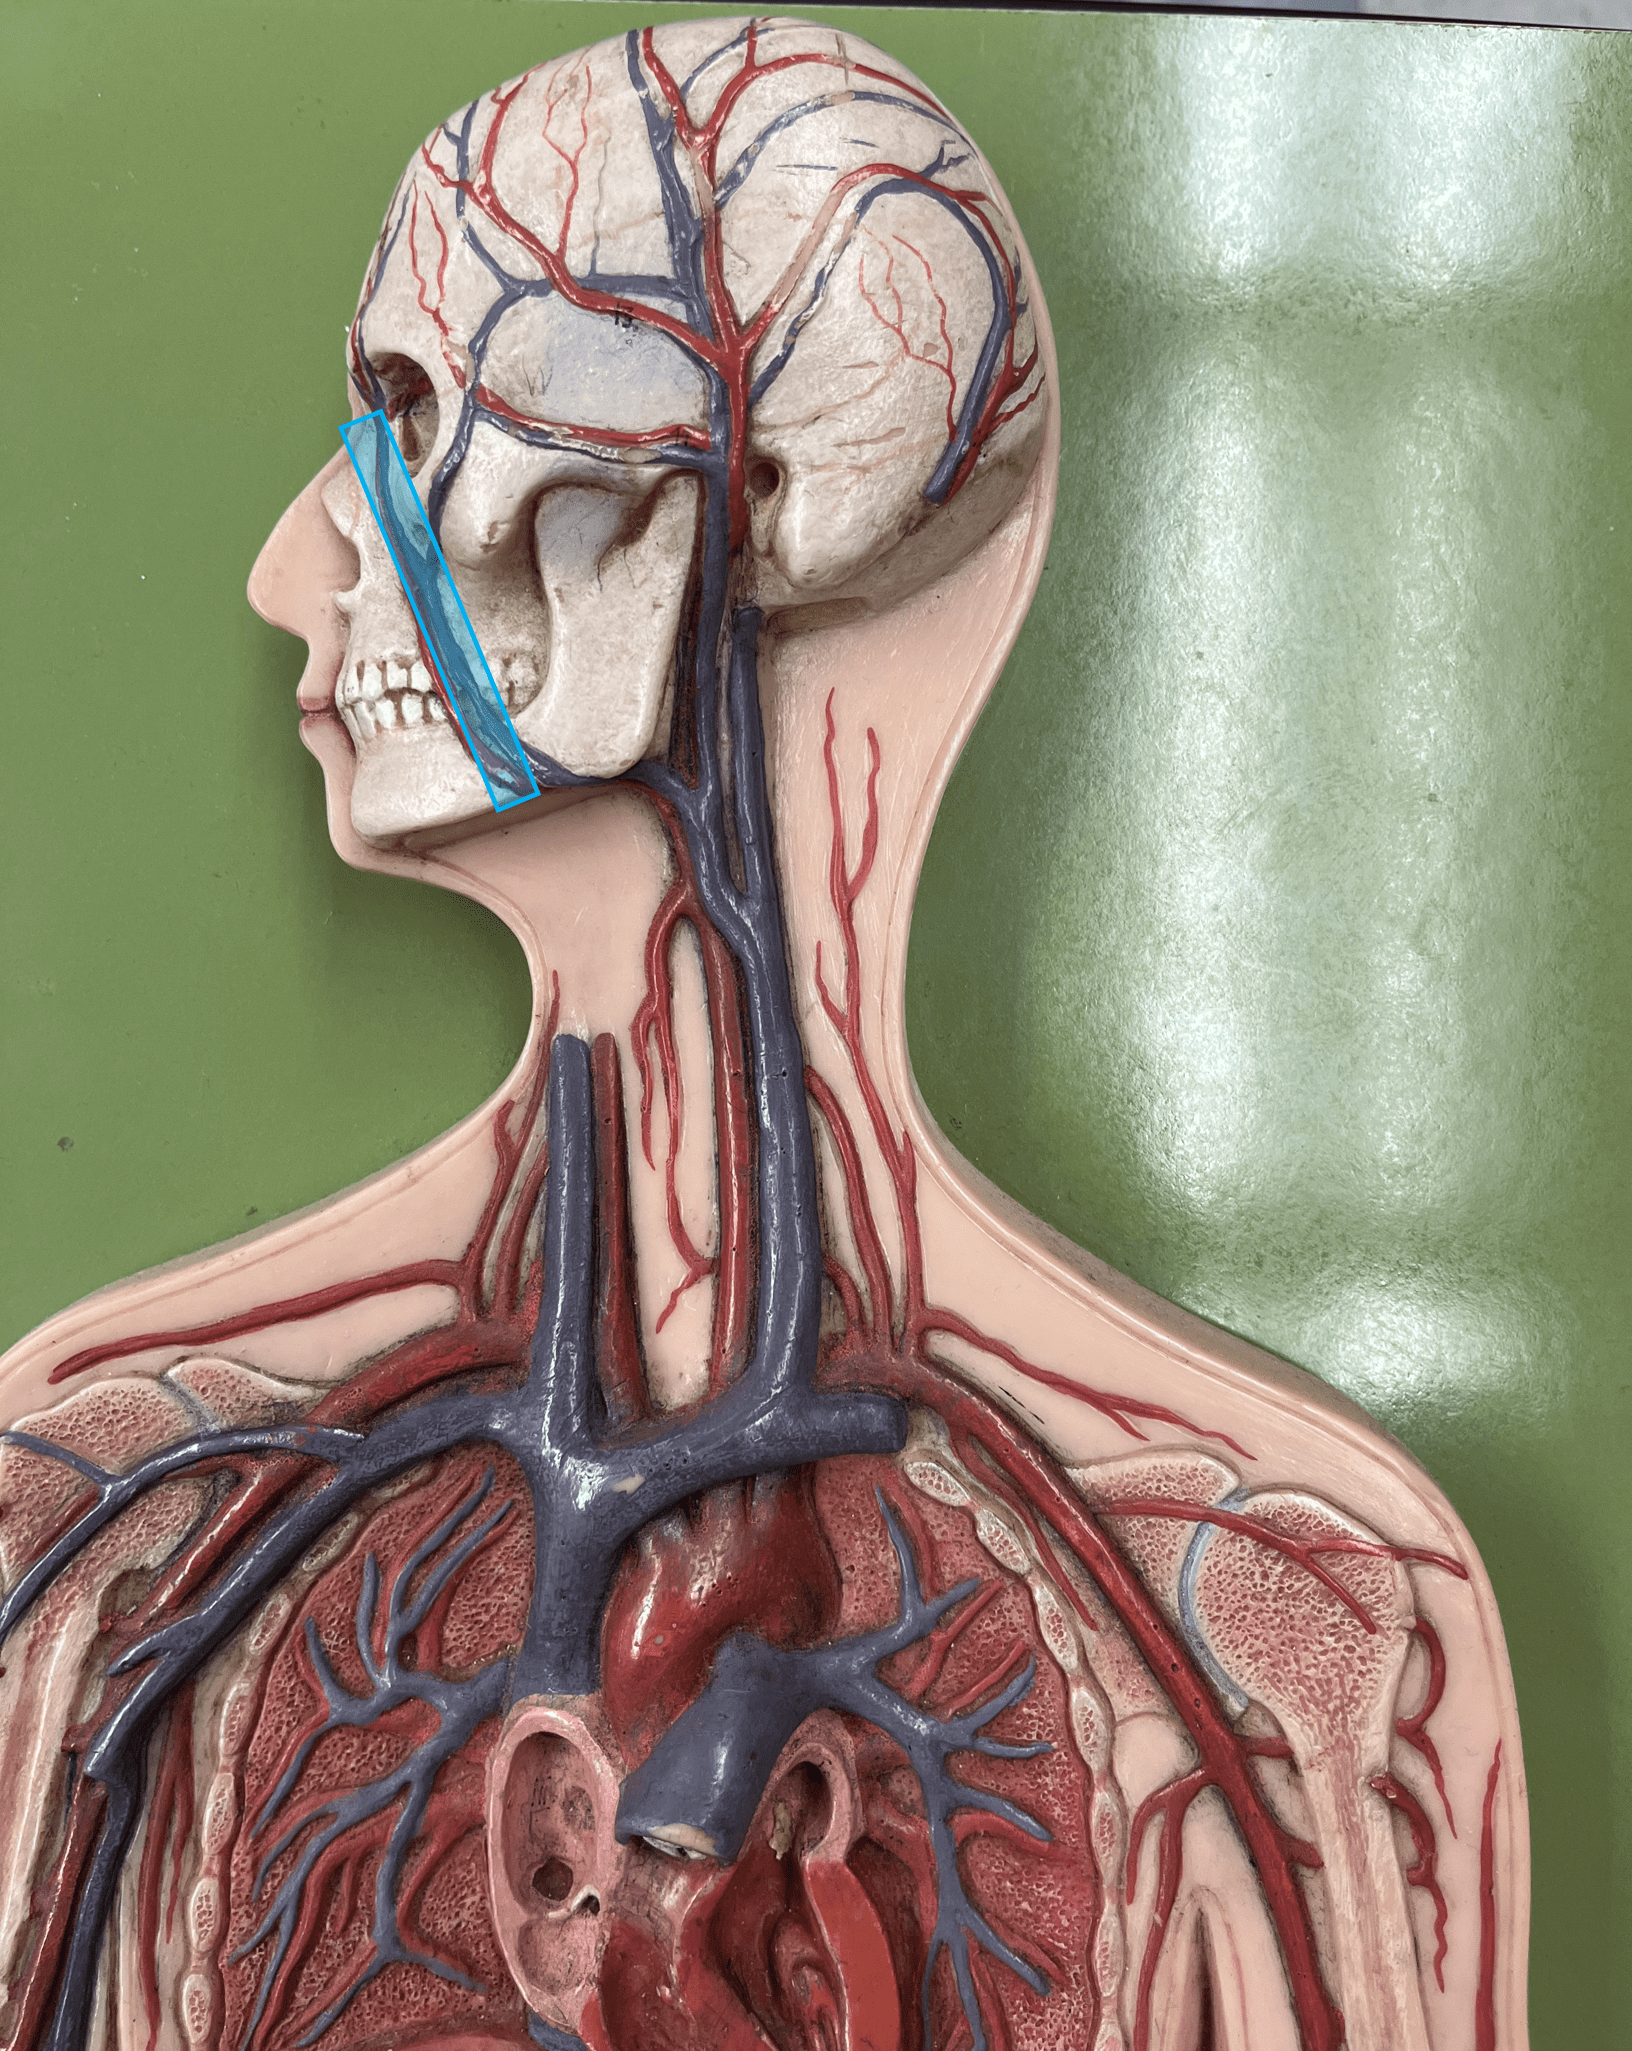

external carotid artery

• An artery of the head and neck.

• Originates from the common carotid artery.

• Supplies the extracranial structures through its branches.

• Laterally, the anteriormost artery of the neck.

• Originates from the common carotid artery.

• Supplies the extracranial structures through its branches.

• Laterally, the anteriormost artery of the neck.

15

New cards

facial artery

• An artery of the head and neck.

• Originates from the external carotid artery.

• Supplies the skin and muscles of the face.

• Originates from the external carotid artery.

• Supplies the skin and muscles of the face.

16

New cards

maxillary artery

• An artery of the head and neck.

• Originates from the external carotid artery.

• Supplies the teeth, maxilla, oral cavity, and external ear.

• Originates from the external carotid artery.

• Supplies the teeth, maxilla, oral cavity, and external ear.

17

New cards

superficial temporal artery

• An artery of the head and neck.

• Originates from the external carotid artery.

• Supplies the chewing muscles, nasal cavity, lateral face and scalp, and dura mater.

• Originates from the external carotid artery.

• Supplies the chewing muscles, nasal cavity, lateral face and scalp, and dura mater.

18

New cards

occipital artery

• An artery of the head and neck.

• Originates from the external carotid artery.

• Supplies the posterior scalp.

• Originates from the external carotid artery.

• Supplies the posterior scalp.